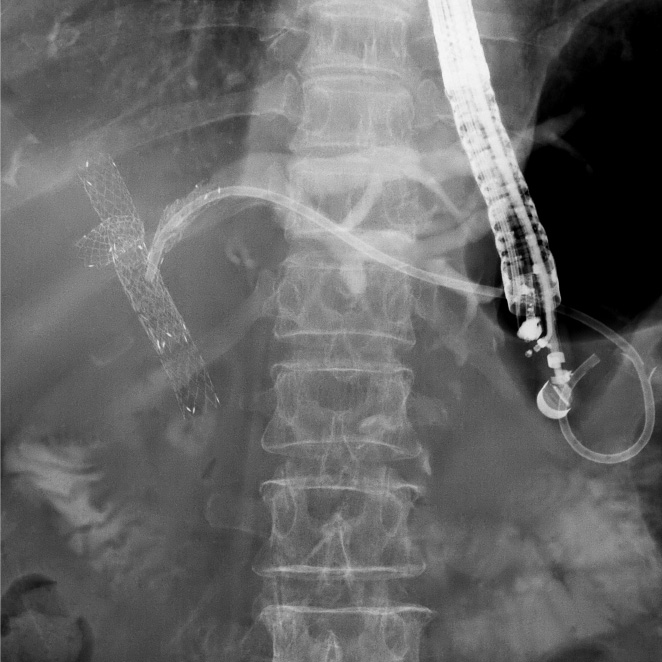

重症急性膵炎後のWONに対するEUS下膿瘍ドレナージ

肝門部胆管癌に対するEUS下胆道ドレナージ

急性胆嚢炎に対するEUS下胆嚢ドレナージ(LAMS留置)